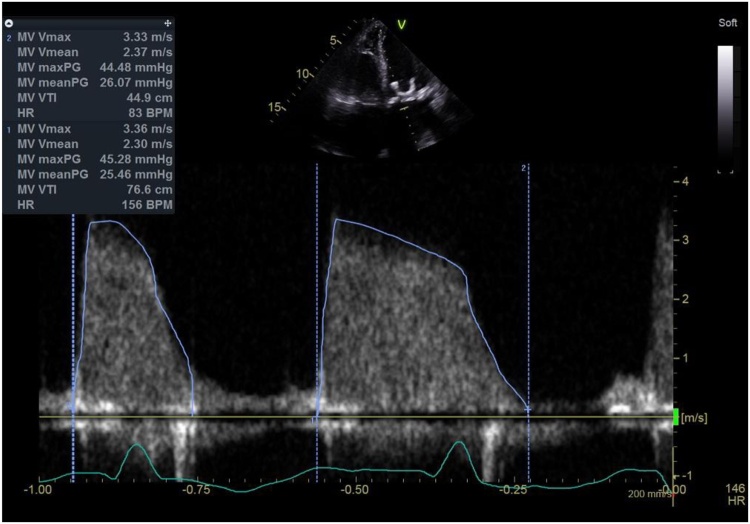

Fig. 3.

Transthoracic apical 4 chamber view with spectral doppler interrogation demonstrating elevated transmittal gradients.